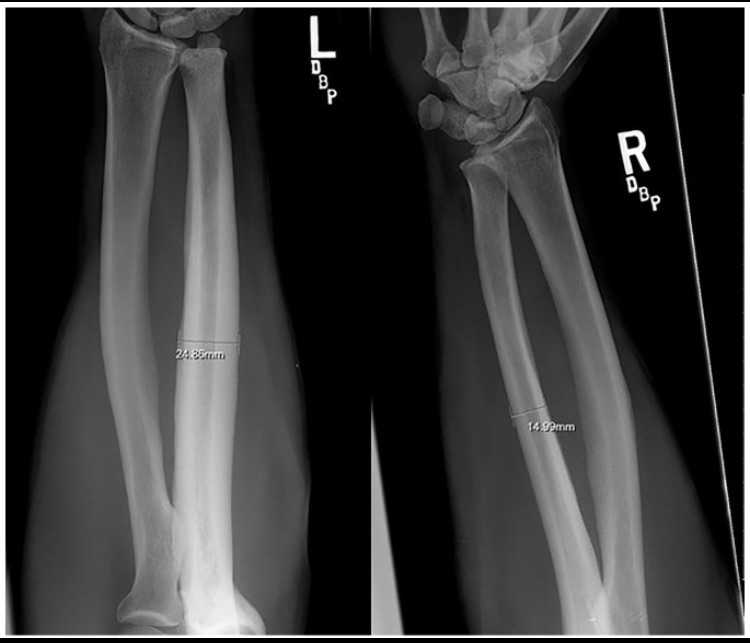

Honestly, this is personally my favorite study to prove the effectiveness of bone smashing. This study was conducted in 1980 on 60 participants, 37 of whom were professional riders without a saddle. Guess what? As I mentioned before, significant bone hypertrophy occurred only in those who practiced horseback riding without a saddle (I explained the reason before, because this type requires the rider’s ulna to hit and contact the hip). To understand more about this process that happens during the race, here is a direct quote from the study:

“On observing a contestant who is riding, the riding arm is noted to contact the anterior iliac crest and the heavily resined chaps (Fig. 3). The event requires strength, timing, balance, and courage. Ideally, the forearm should be tucked against the pelvis and chaps. Failure to maintain this position, resulting in hammering action of the forearm against pelvis and chaps.”

Oh my God, I can’t believe it, the scientists literally wrote “hammering action”! Who would believe this? Hammering movements on the bone cause severe bone hypertrophy. Wait, what does this remind you of? Yes, exactly the same thing you were trying to prove wrong, which is hammering your face. And luckily, the scientists also mentioned that bone hypertrophy occurred due to periosteal inflammation resulting from trauma to the bone. Yes, literally. You can look at the image below and you will notice severe bone hypertrophy at the place where the ulna hits the hip. Oh my God, all this hypertrophy happens in just an 8-second round!!! Just this very short time is enough to cause extreme bone growth. The answer is yes, lol

https://reader.z-library.sk/read/bc...4f5ca2d25511e411cd99274aaa2a01e1e75af408e60e1